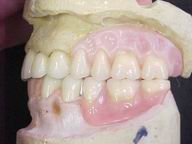

Reabilitação funcional e estética em ambas as arcadas

com próteses fixas e removíveis de encaixe de precisão.

Vista Oclusal Sobre Modelos de Gesso